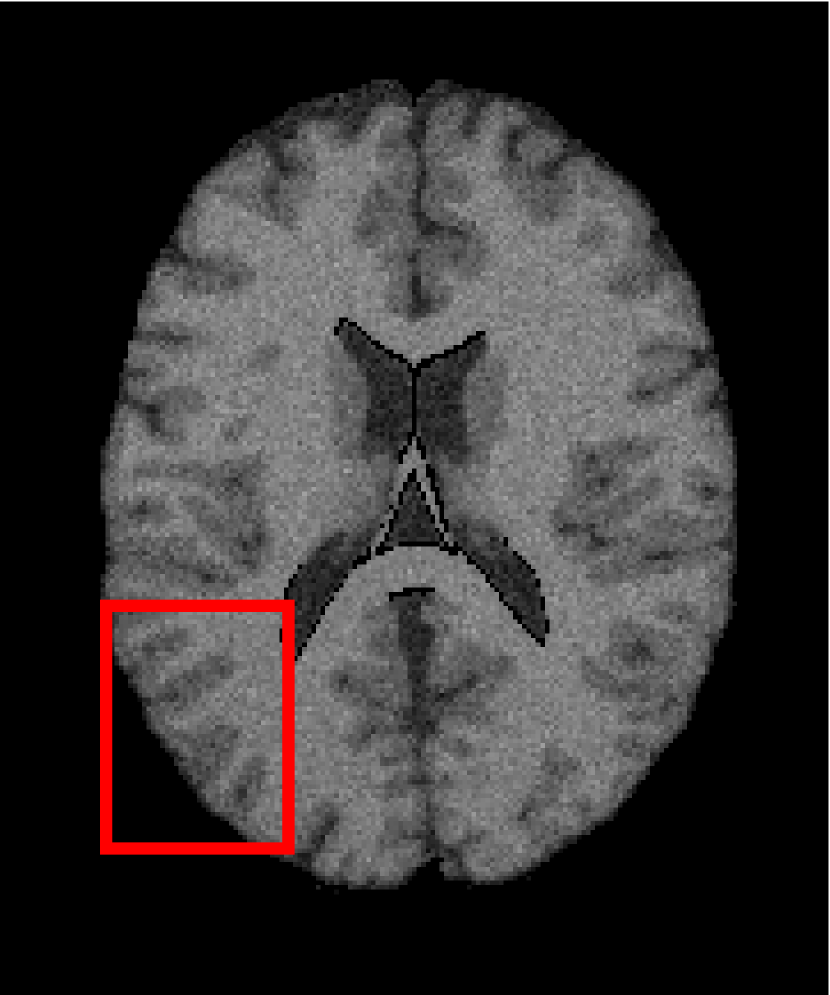

4.4.2 Results on Medical Images

Next, we representatively segment five medical images from BrianWeb. They are represented as five slices in the axial plane with a sequence of 70, 80, 90, 100 and 110, which are generated by T1 modality with slice thickness of 1mm resolution, 9% noise and 20% intensity non-uniformity. Here, we set c=4𝑐4c=4 for all cases. The comparison between WRFCM and its peers are shown in Fig. 9 and Table II. The best values are in bold.

Figure 9: Segmentation results on five medical images. The parameter: ϕ=5.35italic-ϕ5.35\phi=5.35. From top to bottom: noisy images, ground truth, and results of FCM_S1, FCM_S2, FLICM, KWFLICM, FRFCM, WFCM, DSFCM_N, and WRFCM.

By a view of the marked red square in Fig. 9, we find that FCM_S1, FCM_S2, FLICM, KWFLICM and DSFCM_N are vulnerable to noise and intensity non-uniformity. They give rise to the change of topological shapes to some extent. Unlike them, FRFCM and WFCM achieve sufficient noise removal. However, they produce overly smooth contours. Compared with its seven peers, WRFCM can not only suppress noise adequately but also acquire accurate contours. Moreover, it yields the visual result closer to ground truth than its peers. As Table II shows, WRFCM obtains optimal SA, SDS and MCC results for all five medical images. As a conclusion, it outperforms its peers visually and quantitatively.